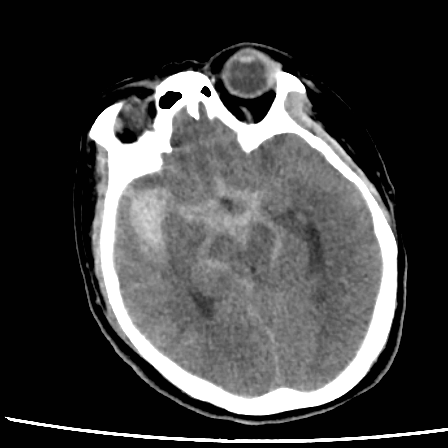

病史:中年女性,新冠感染,颅内动脉瘤破裂,Hunt-Hess 4级